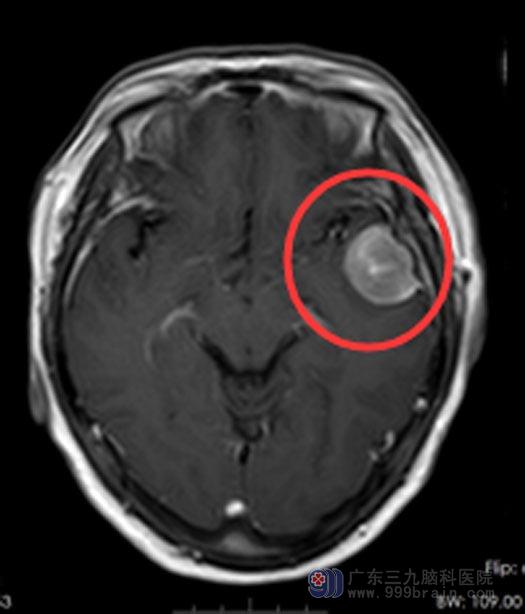

进一步检查发现肿瘤较之前有所增大,考虑脑膜瘤,家属同意手术治疗。鲁明主任主刀在全麻下行“左侧颞部脑膜瘤切除术+硬脑膜修补术+颅骨成形术”,显微镜下顺利将肿瘤全切除。术后病理:左颞过渡型脑膜瘤,WHO1级。

手术前